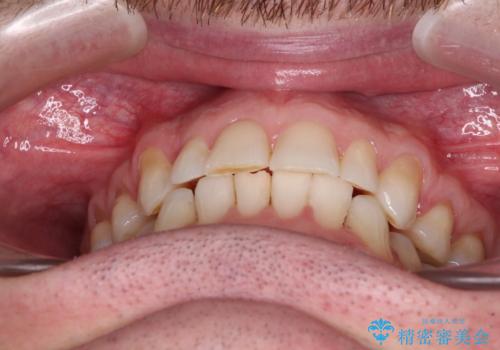

- 上下前歯の叢生を気にして来院された患者様です。

抜歯矯正をした後戻りということで、歯列不正はそれほど大きくなかったため、インビザライン・ライトを用いて矯正治療を行うこととしました。

前歯のデコボコが残っており、シミュレーション通りに動いていない部分がありましたが、再矯正であることやご本人の満足いくところまでデコボコが改善されたとのことで、治療を終了することとしました。